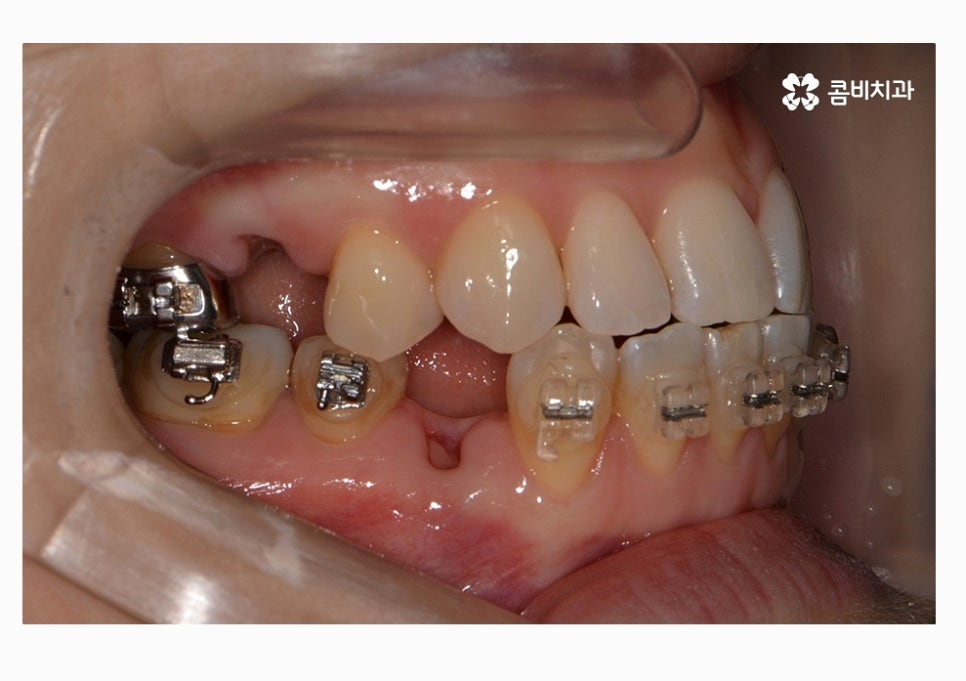

부정교합의 종류도 다양하지만 오늘 보시는 케이스의 경우

절단교합 + 3급부정교합에 해당하며 아랫니가 과하게 앞으로

돌출된 경우에는 치열뿐 아니라 주걱턱과 같이

얼굴형에도 영향을 줄 수 있어요.

치열 사진을 볼 때 정면보다는 옆모습으로 볼 때

아래 어금니가 위 어금니보다 앞으로 나와있고

앞니 교합이 제대로 맞물리지 않는다는 것이 눈에 띄게 나타나는데

이번 케이스의 환자분의 경우에는 3급 부정교합과 절단교합을 치료하기 위해서

콤비교정을 시작하기 전에 발치를 먼저 진행하였는데

위 환자분의 경우에는 콤비교정의 치료 경과를 보면

아랫니가 정상교합이 되었고 치열도 보다 가지런하게

변화되고 있음을 알 수 있는데요.